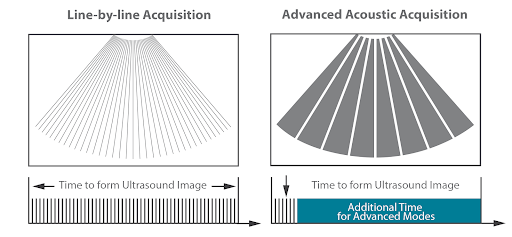

Получение усовершенствованных акустических изображений

За счет передачи и получения сигнала от сравнительно небольшого количества крупных зон при получении усовершенствованных акустических изображений извлекается больше информации для каждого кадра и построение изображения происходит в 10 раз быстрее, чем при традиционном способе построчной визуализации.